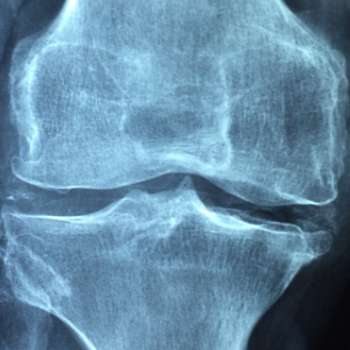

무릎에 물이차는 원인 3. 퇴행성 관절 질환

- 퇴행성 관절 질환은 무릎 관절의 연골이 시간이 지남에 따라 닳아지고 손상되는 상태를 포함합니다. 주로 고령자에서 발생하며, 연골의 감소로 인해 무릎 관절 내에 물이 찰 수 있는 조건이 형성됩니다. 이는 관절을 보호하는 기능을 약화시키고 물이 축적되게 합니다.

무릎에 물이차는 원인 4. 연골 손상

- 무릎의 연골은 관절을 부드럽게 움직이게 하고 충격을 흡수하는 역할을 합니다. 그러나 부상, 과도한 스포츠 활동, 나이 등의 요인으로 인해 연골이 손상될 수 있습니다. 연골 손상으로 인해 관절에서 마찰이 증가하면서 염증이 발생하고, 이로 인해 물이 찰 수 있습니다.

무릎에 물이차는 원인 8. 류마티스성 관절염 (Rheumatoid Arthritis)

- 무릎 관절을 포함한 여러 관절을 영향을 주는 면역 체계의 과도한 반응으로 인해 발생하는 염증성 관절 질환입니다. 무릎에 염증이 발생하면 관절 주위의 혈관이 확장되어 독소와 유체가 축적될 수 있습니다. 이로 인해 물이 차고 부음이 발생하며, 무릎의 움직임에 제약이 생길 수 있습니다. 또한, 무릎 통증과 함께 조인트 디폼리티(관절 형태의 변형)가 나타날 수 있습니다.